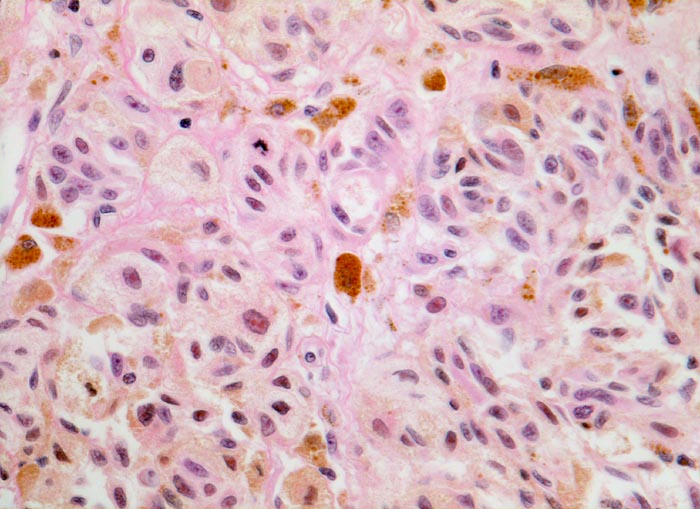

Atypische pigmentierte Zellen mit reichlich Zytoplasma und vergrösserten atypischen Kernen mit prominenten eosinophilen Nukleolen. Mitose. Zwischen den Tumorzellen Melanophagen mit grobgranulärem intrazytoplasmatischem Pigment.

Der Nachweis von Mitosen in intradermal gelegenen Melanozyten spricht für das Vorliegen eines malignen Melanoms.